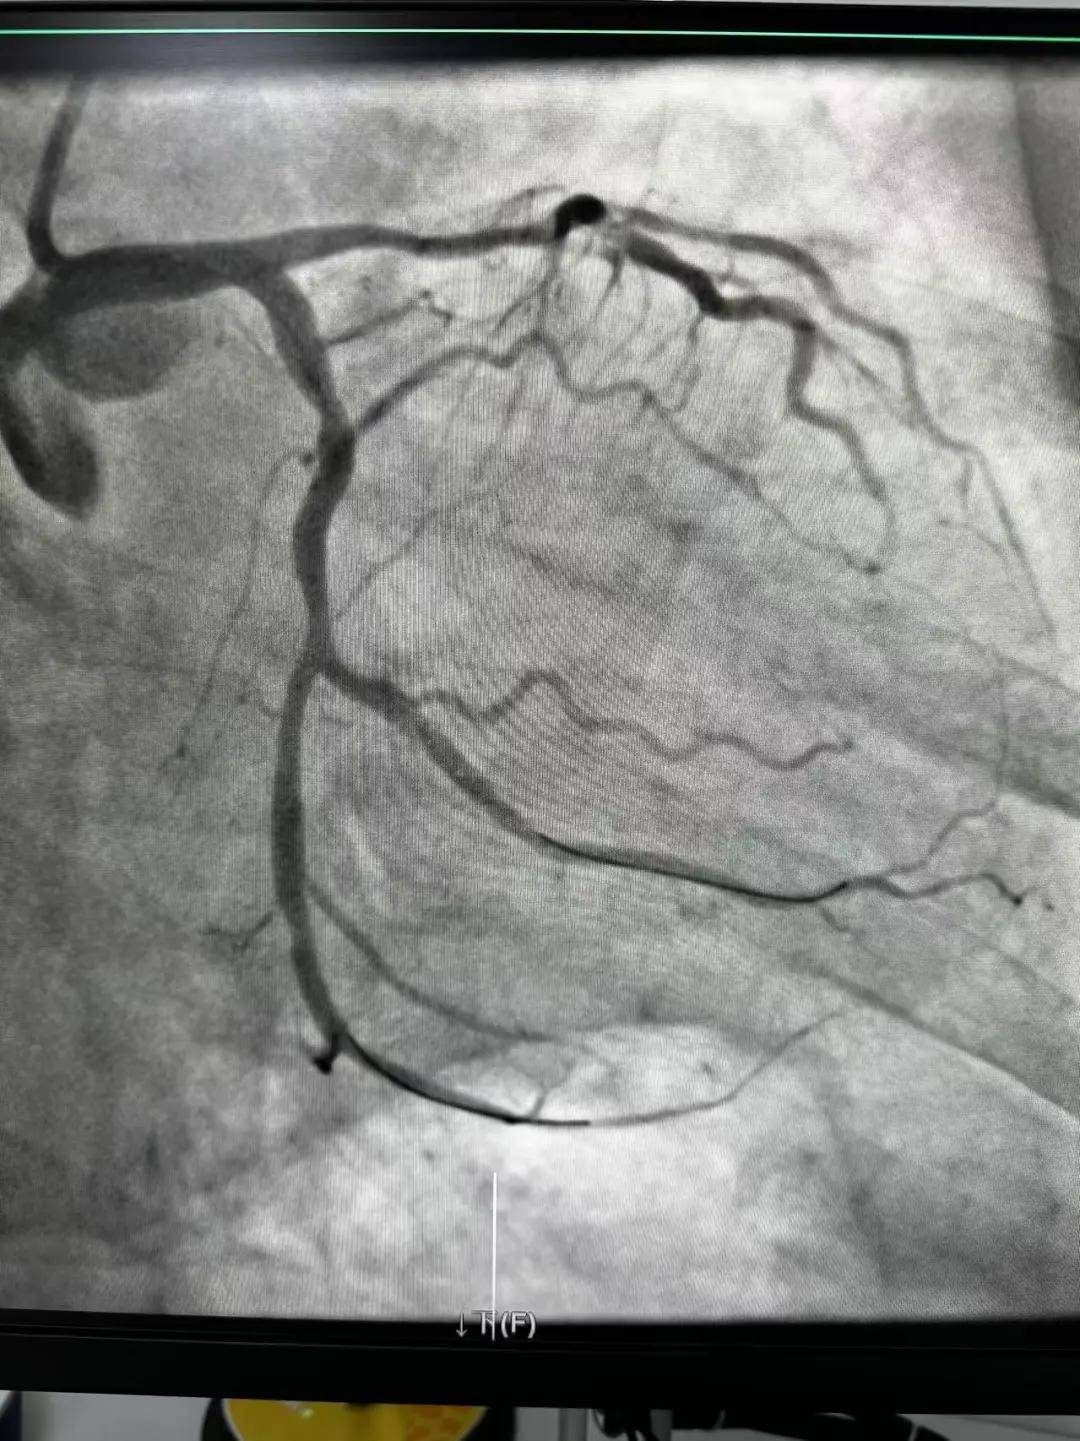

今天最后一臺手術(shù),是一個嚴重三支病變的病人,患者張大爺,71歲,以“突發(fā)胸悶胸痛3小時”為主訴入院。經(jīng)心電圖檢查后示室上性心動過速,以“冠心病、心絞痛、心律失?!睘樵\斷收住入心內(nèi)科。心內(nèi)科團隊通過審慎評估,決定給予患者冠狀動脈造影術(shù)及冠狀動脈內(nèi)支架置入術(shù)。

手術(shù)開臺,在王云峰主任的帶領(lǐng)下,心內(nèi)科團隊為張大爺進行穿刺。由于病人重聽,在手術(shù)臺上配合度不高,加上病情嚴重,導(dǎo)致手術(shù)難度加大。手術(shù)正在緊張進行中,導(dǎo)管室內(nèi)線電話又急促響起!一位急性心肌梗死患者情況危急,需要緊急進行介入治療。

許先生,52歲,大貨司機,在鶴壁至安陽卸貨過程中,突發(fā)胸悶胸痛,伴大汗1.5小時。 患者繞行安陽,于11點38分到達我院大門,11點41分首份心電圖,提示患者下壁心肌梗死。 起病急,病程短,情況十分危險,如果血管完全堵塞將直接威脅患者生命,亟需疏通堵塞血管進行血運重建。

穿刺、造影、放支架……兩個手術(shù)間各個環(huán)節(jié)緊張卻有序地進行著!在心內(nèi)科團隊精準、默契的配合下,兩臺手術(shù)順利完成! 兩名患者的快速、同時、成功救治,得益于殷都區(qū)人民醫(yī)院醫(yī)務(wù)人員快速的應(yīng)急能力、過硬的急救技能,同時更得益于導(dǎo)管室同開臺,保障了救治的迅速有效。